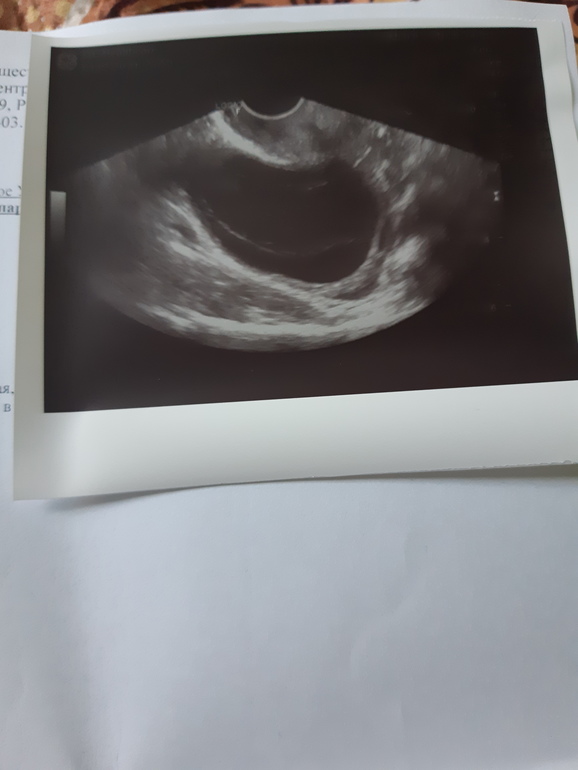

вот такая "прелесть " выросла(((( только вот не слова о том КЖТ ли это нет,но толстостенные кисты -это кисты жёлтого тела. Завтра сдам хгч,вернее попробую с этими праздниками и к гинекологу.

Фолликулярная она тонкостенная,а у меня толстостенная это не она,хотя мне уже все равно,надо хгч сдать,потом отпишусь)))